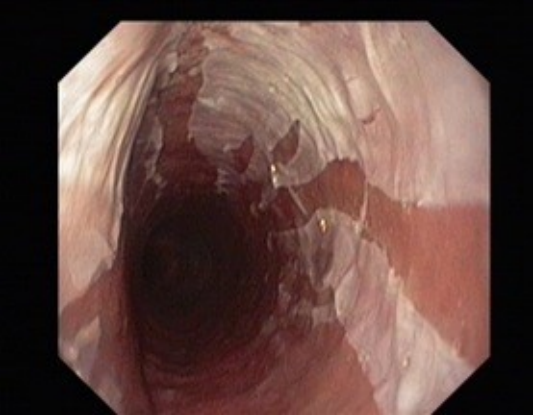

内镜下的典型表现是黏膜脱落。

EGD显示,食管内壁可见易剥离的白色纵向组织贯穿整个食管,止于食管胃交界处,其下层黏膜充血和红斑(图1和图2)。